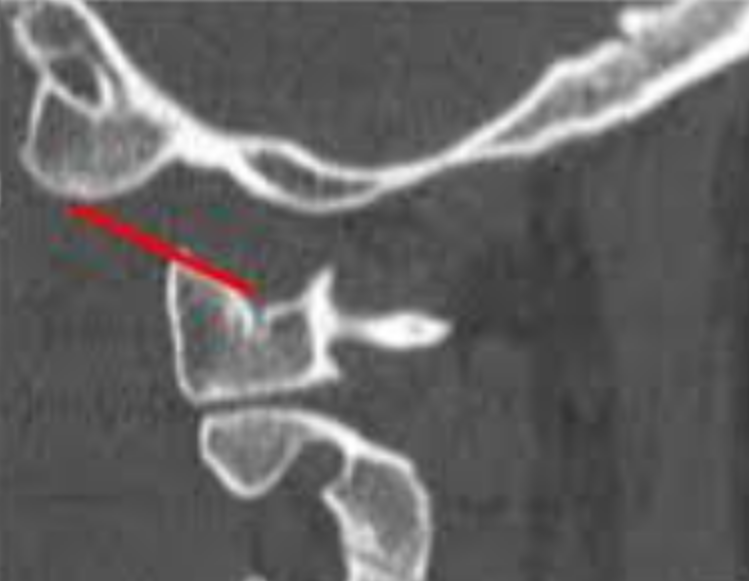

CCI measures the joint space between the occipital condyles and the lateral masses of C1. It is currently considered the most reliable CT-based metric for diagnosing occipitoatlantal dissociation.

• Use coronal CT reconstructions.

• Measure the distance between each occipital condyle and the corresponding C1 superior articular surface.

• Record the maximum value or the mean, depending on institutional protocol.

• Normal: ≤2 mm

• 2 mm widening is diagnostic of occipital-C1 dissociation, even in the absence of gross displacement.